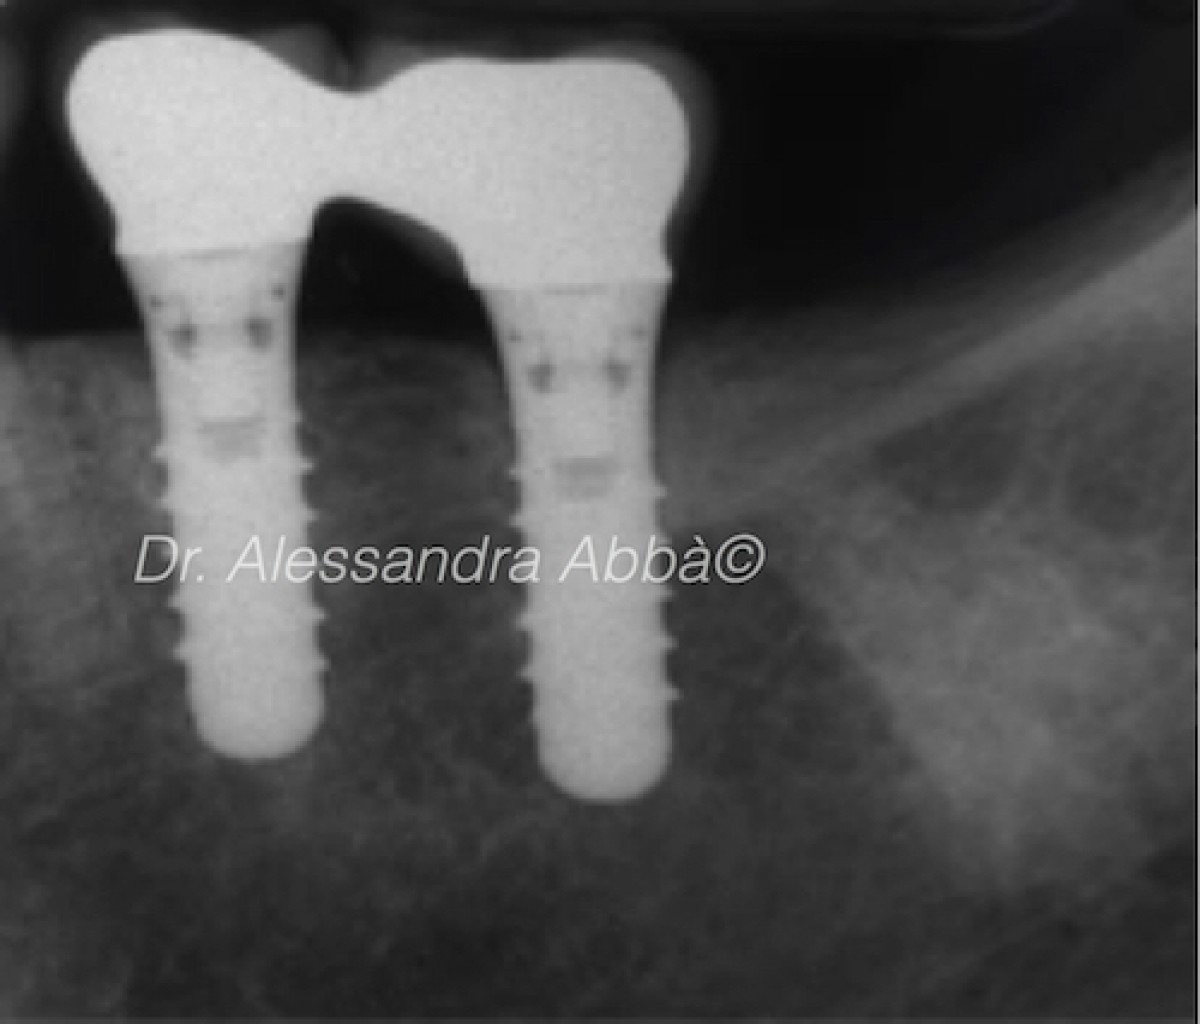

Early implant failures typically occur before or at the abutment connection and are generally associated with minor peri-implant bone loss. Late implant failures, in contrast, occur after occlusal loading and are often associated with extensive peri-implant bone loss. Available evidence suggests that early failure rates (0.76% to 7.47%) are somewhat lower than late (5 to 10 years) implant failure rates (2.1% to 11.3%). But what is the survival rate of implants placed in sites where implant failure has already occurred and what are the factors that could influence the subsequent outcomes of reprocessing?

The weighted mean survival rate for implants after retreatment was 86.3%, with follow-up ranging from less than 1 year to over 5 years. The survival rates of smooth-surfaced and rough-surfaced implants were compared in 217 retreated implants, revealing a significantly higher survival rate for rough-surfaced implants than for smooth-surfaced implants, 90% versus 68.7%. Insufficient data were available to evaluate the effect of patient- or treatment-related characteristics on the survival of implants after retreatment.

From the data of this study, which must be confirmed in other similar studies, it can be concluded that the survival rate of the re-inserted implants is lower than that generally reported for the initial positioning of the implant. Higher survival rates have been reported with rough surface implants than with smooth surface implants in re-insertion cases.

The re-insertion of implants in sites where implant failure has already occurred has a relatively high survival rate of 86.3% with follow-up ranging from less than 1 year to over 5 years. The risk factors associated with initial implant failures, such as implant architecture, anatomical site, infection and occlusal overload, must be well re-evaluated and modified at the time of the new implant insertion.